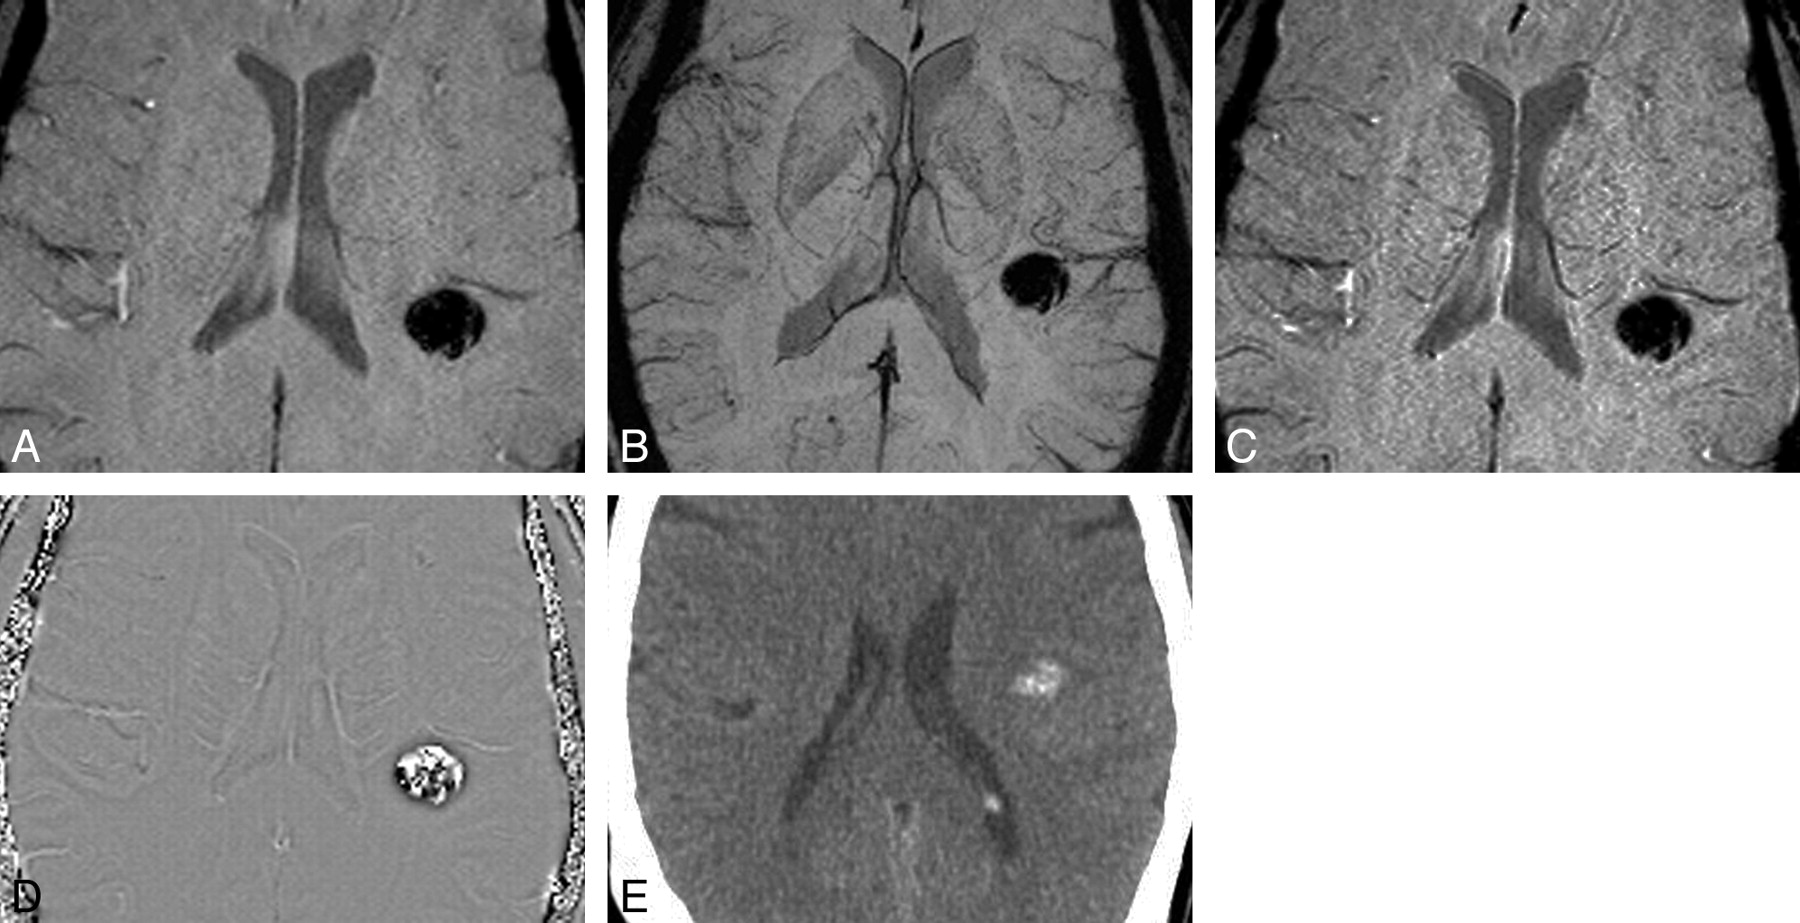

Value of phase imaging in identifying calcification in OD. Magnitude (A), mIP (B), and SWI (C) images do not help distinguish iron-containing hemorrhage from calcification in this tumor. D, Phase image shows high signal intensity centrally identifying calcification. E, CT image shows faint hyperattenuation, which had persisted for months and represented calcified tumor.